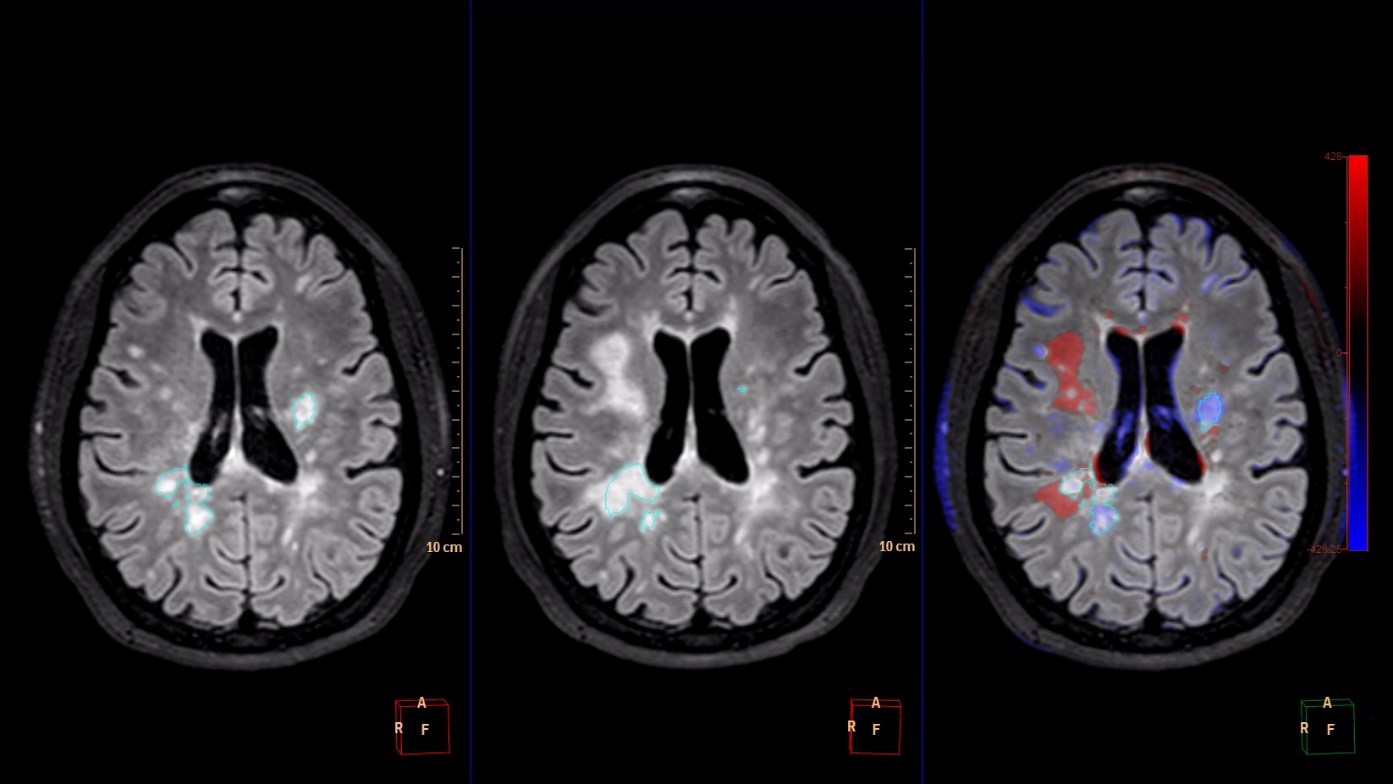

IntelliSpace Portal 9.0 offers Longitudinal Brain Imaging (LoBI), an application to help clinicians visualize subtle differences in the brain images of the same individual across time, which may be used by clinicians as the assessment of neurological disease progression. Multiple images are automatically aligned and registered to simplify comparison, and the application provides editing tools and volumetric quantification. Comparative Brain Imaging (CoBi) functionality even allows users to track subtle differences in the brain by subtracting scans taken at different points in time.

Technology that detects subtle differences in the brain over long periods of time may help in the assessment of neurological disease progression.